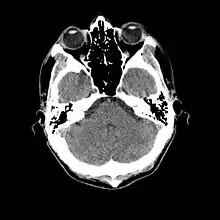

A TC baseia-se nos mesmos princípios que a tomografia convencional, segundo os quais tecidos com diferentes composições absorvem a radiação X de forma diferente. Ao serem atravessados por raios X, tecidos mais densos (como o fígado) ou com elementos mais pesados (como o cálcio presente nos ossos), absorvem mais radiação que tecidos menos densos (como o pulmão, que está cheio de ar).[1][3]

Assim, uma TC indica a quantidade de radiação absorvida por cada parte do corpo analisada (radiodensidade), e traduz essas variações numa escala de cinzentos, produzindo uma imagem. Cada pixel da imagem corresponde à média da absorção dos tecidos nessa zona, expresso em unidades de Hounsfield, em homenagem ao criador da primeira máquina de TC.

Em relação às imagens, existe uma convenção para traduzir os valores de voltagem detectados em unidades digitais. Dessa forma, temos valores que variam de –1000, onde nenhuma voltagem é detectada: o objeto não absorveu praticamente nenhum dos fótons de raio-X, e se comporta como o ar; ou um valor muito alto, algo como +1000 ou mais, caso poucos fótons cheguem ao detector: o objeto absorveu quase todos os fótons de raio-X. Essa escala onde –1000 é mais escuro, 0 é um cinza médio e +1000 (ou mais) é bem claro. Dessa forma quanto mais raio-X o objeto absorver, mais claro ele é na imagem. Outra vantagem é que esses valores são ajustados de acordo com os tecidos biológicos.

A escala de cinza é formada por um grande espectro de representações de tonalidades entre branco, cinza e o preto. A escala de cinzas é que é responsável pelo brilho de imagem. Uma escala de cinzas foi criada especialmente para a tomografia computadorizada e sua unidade foi chamada de unidade Hounsfield , em homenagem ao cientista que desenvolveu a tomografia computadorizada. Nesta escala temos o seguinte:

- zero unidades Housfield (0 HU) é a água,

- ar -1000 (HU);

- osso de 700 HU(osso esponjoso) a 3000 HU(osso denso);

- gordura de –100 a -50 HU;

- músculo de 10 a 40 HU

O uso de diferentes janelas em tomografia permite por exemplo o estudo dos ossos com distinção entre a cortical e a medular óssea ou o estudo de partes moles com a distinção, por exemplo, no cérebro entre a substância branca e a cinzenta. A mesma imagem pode ser mostrada com diferentes ajustes da janela, de modo a mostrar diferentes estruturas de cada vez. Não é possível usar um só ajuste da janela para ver, por exemplo, detalhes ósseos e de tecido adiposo ao mesmo tempo.

As imagens tomográficas podem ser obtidas em dois planos básicos: o plano axial (perpendicular ao maior eixo do corpo) e o plano coronal (paralelo a sutura coronal do crânio ou seja é uma visão frontal). Após obtidas as imagens, recursos computacionais podem permitir reconstruções no plano sagital (paralelo a sutura sagital do crânio) ou reconstruções tridimensionais.